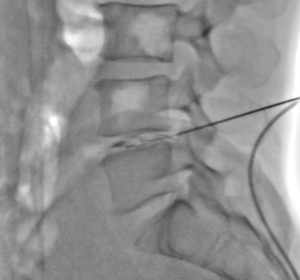

Scopie de profil infiltration intra discale

Pour le geste le patient est positionné sur le ventre, si cette position est inconfortable, il est préférable de réaliser le geste sous sédation anesthésique. Une anesthésie locale de la peau et du trajet est réalisée pour mettre en place une aiguille sous guidage scopique dans la partie centrale du disque.

Une fois en place, une première injection de produit de contraste permet de confirmer le positionnement et de s'assurer de l'absence d'opacification vasculaire qui contre-indiquerait l'injection de corticoïdes particulaires.